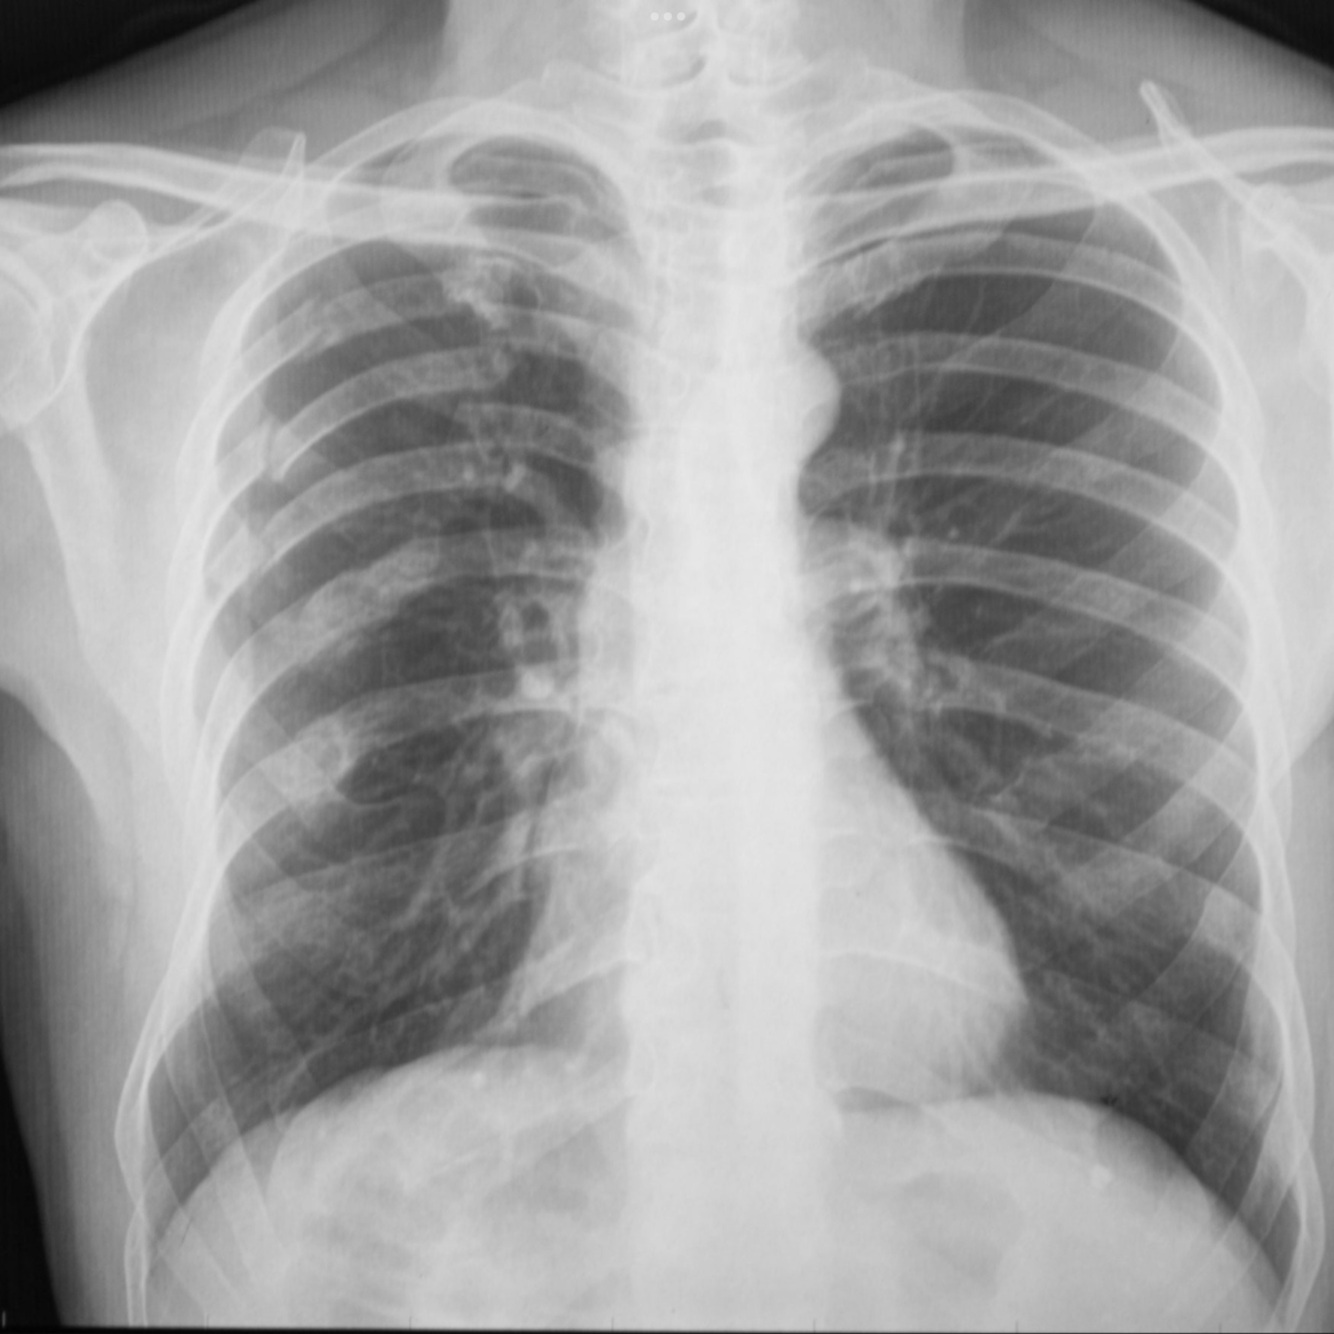

Q

Masculino de 66 años de edad, cuenta con el diagnóstico de VIH positivo, con fiebre, disnea

A

TB Miliar